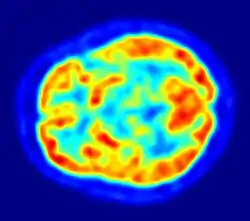

La TEP repose sur le principe général de la scintigraphie qui consiste à injecter un traceur dont on connaît le comportement et les propriétés biologiques pour obtenir une image du fonctionnement d'un organe ou la présence d'une cible moléculaire. Ce traceur est marqué par un atome radioactif (carbone, fluor, azote, oxygène, etc.) qui émet des positons dont l'annihilation produit deux photons. C'est la détection en coïncidence de ces photons qui permet la localisation de leur site d’émission et donc la concentration du traceur en chaque point de l'organe. C'est cette information quantitative que l'on représente sous la forme d'une image faisant apparaître en couleurs les zones de forte concentration du traceur.

Ainsi, la TEP permet de visualiser les activités du métabolisme des cellules : on parle d'imagerie fonctionnelle par opposition aux techniques d'imagerie dite structurelle comme celles basées sur les rayons X (radiologie ou CT-scan scanner) qui réalisent des images de l'anatomie. Par conséquent, la tomographie par émission de positons est un outil diagnostique qui permet de déceler certaines pathologies qui se traduisent par une altération de la physiologie normale comme les cancers, mais aussi les démences par exemple.

Le principe de l'utilisation de la TEP en imagerie cérébrale (neurologie et neurosciences cognitives) repose sur le lien entre activité des neurones dans une région donnée et la mesure de la radioactivité. Ce lien est indirect puisqu'au travers de la TEP, on mesure l'accumulation d'un radiotraceur. Le radiotraceur le plus couramment utilisé est le FDG qui mesure la consommation de glucose des neurones. En recherche on a aussi pu utiliser l'oxygène 15 dont l'accumulation est due à la réponse hémodynamique, c'est-à-dire une augmentation locale du débit sanguin cérébral qui se produit lorsqu'une région du cerveau voit son activité augmenter. L'imagerie cérébrale TEP reflète donc l'apport d'énergie régionale mais elle est très liée à l'activité cérébrale proprement dite.

Aujourd'hui la TEP au FDG peut-être utilisée en routine clinique pour le diagnostic des maladies cérébrales dégénératives comme la maladie d'Alzheimer. De nombreuses études récentes ont démontré l’intérêt de l’utilisation de la TEP pour un diagnostic précoce de la maladie d’Alzheimer et pour le diagnostic différentiel d'une démence ou d'un déficit cognitif léger (MCI). On observe des réductions du métabolisme glucidique au niveau de régions spécifiques selon les pathologies en cause.